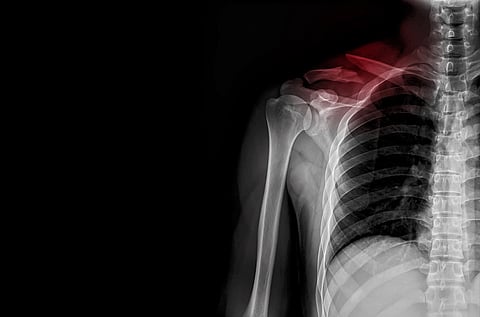

Key TakeawaysThe hospitalization rate for child broken collarbones has more than doubledThis indicates kids are suffering more severe fractures, researchers saidFootball and bed falls are the two most common causes of clavicle fractures.WEDNESDAY, July 9, 2025 (HealthDay News) — More kids are being hospitalized for broken collarbones, a new study has found.In fact, the hospitalization rate for broken collarbones more than doubled among children between 2014 and 2021, researchers reported.This increase occurred even though the overall rate of childhood clavicle fractures remained relatively stable during the past 10 years, researchers said.“This suggests that while the rate of clavicle fractures is stagnant, the severity of these fractures is rising,” wrote the research team led by Charu Jain, a student at the Icahn School of Medicine at Mount Sinai in New York City.For the study, researchers analyzed records from an injury surveillance database representing about 100 ERs in the United States, looking for collarbone fractures among kids 18 and younger.They wound up examining more than 391,000 cases of broken collarbone that occurred between 2014 and 2023.The hospitalization rate for broken collarbones rose to a high of 2.6% in 2021 from a low of 0.8% in 2014, researchers report.This jibes with previous studies that found more kids require metal implants to properly set their broken collarbones, indicating the fractures are too severe to be treated with a simple sling or cast, researchers said. The study also found that younger kids are more likely to sustain a broken collarbone falling out of bed, while tweens and teens more often suffer breaks playing sports like football, results show.Although 45% of broken collarbones occurred in children younger than 10, that age group accounted for more than 97% of fractures related to beds or bed frames, results show.“Among younger children, there has been an increase in bed-related falls causing clavicular fractures,” senior researcher Dr. Sheena Ranade, an associate professor of orthopedics at Mount Sinai, said in a news release.“Just as there has been a strong emphasis on safe sleep for infants, this study shows that attention should be placed in safe sleeping environments for toddler-aged children to prevent falls out of bed,” Ranade said.On the other hand, children 11 to 18 represented 84% of all collarbone fractures that came from playing football, researchers found.The most common causes of clavicle fractures overall were football (17%), falling from bed (11%), soccer (7%) and bicycles (7%), results show.“Understanding common mechanisms like sports injuries and falls from beds can help guide targeted prevention strategies and parent education,” Jain said.The new study appears in the journal JSES: Reviews, Reports & Techniques.More informationThe Cleveland Clinic has more on broken collarbone.SOURCES: Mount Sinai, news release, July 3, 2025; JSES: Reviews, Reports & Techniques, June 14, 2025 .What This Means For YouParents should be aware of the broken bone risk from bed falls and youth sports..Sign up for our weekly HealthDay newsletter